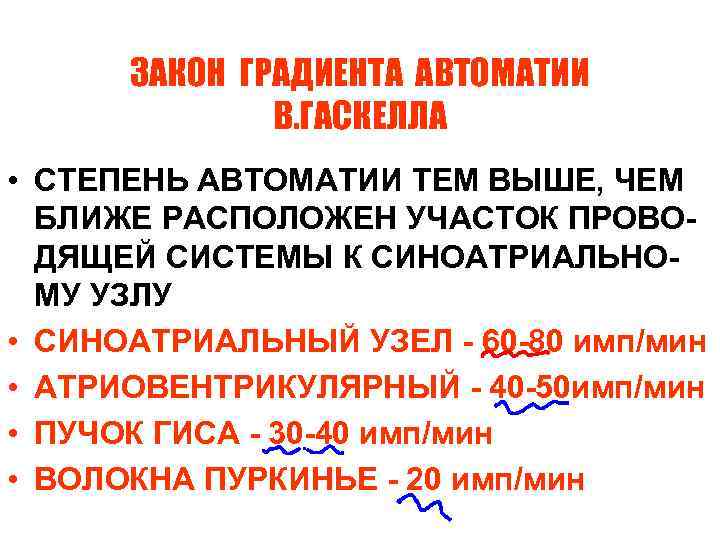

ЗАКОН ГРАДИЕНТА АВТОМАТИИ В. ГАСКЕЛЛА • СТЕПЕНЬ АВТОМАТИИ ТЕМ ВЫШЕ, ЧЕМ БЛИЖЕ РАСПОЛОЖЕН УЧАСТОК ПРОВОДЯЩЕЙ СИСТЕМЫ К СИНОАТРИАЛЬНОМУ УЗЛУ • СИНОАТРИАЛЬНЫЙ УЗЕЛ - 60 -80 имп/мин • АТРИОВЕНТРИКУЛЯРНЫЙ - 40 -50 имп/мин • ПУЧОК ГИСА - 30 -40 имп/мин • ВОЛОКНА ПУРКИНЬЕ - 20 имп/мин

ЗАКОН ГРАДИЕНТА АВТОМАТИИ В. ГАСКЕЛЛА • СТЕПЕНЬ АВТОМАТИИ ТЕМ ВЫШЕ, ЧЕМ БЛИЖЕ РАСПОЛОЖЕН УЧАСТОК ПРОВОДЯЩЕЙ СИСТЕМЫ К СИНОАТРИАЛЬНОМУ УЗЛУ • СИНОАТРИАЛЬНЫЙ УЗЕЛ - 60 -80 имп/мин • АТРИОВЕНТРИКУЛЯРНЫЙ - 40 -50 имп/мин • ПУЧОК ГИСА - 30 -40 имп/мин • ВОЛОКНА ПУРКИНЬЕ - 20 имп/мин